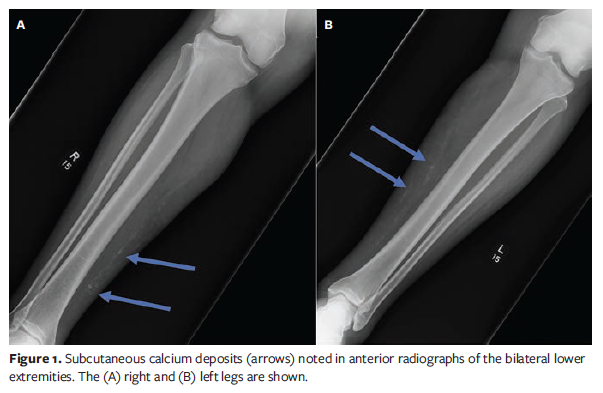

Calcific arteriolopathy is a subtype of calcinosis cutis, a disease process that involves the deposition of insoluble calcium salts in tissue.1 Unlike other variants of calcinosis cutis in which calcium is deposited in the skin and soft tissue, calcific arteriolopathy also involves deposition of calcium in the arteries and arterioles of the soft tissues; this leads to ischemia, thrombosis, and cutaneous necrosis. Vascular ischemia can present clinically as violaceous nodules, plaques, retiform purpura, and ulceration. Calcinosis may also be evident as a histologic or radiologic finding (Figure 1); however, biopsy of lesions is considered the primary diagnostic modality.2 Pain is a distinguishing feature and can be disproportionate to observed cutaneous findings.

Radiographs indicated calcium deposition in the soft tissue and arteries (Figure 1). The patient was diagnosed with NUC and started STS infusions 25 mg IV 3 times per week co-administered with ondansetron. Following discharge, the patient attempted to manage her wounds at home owing to significant transportation time to the hospital and wound center; however, she continued to experience difficulty with thorough cleansing of the wounds because of pain.